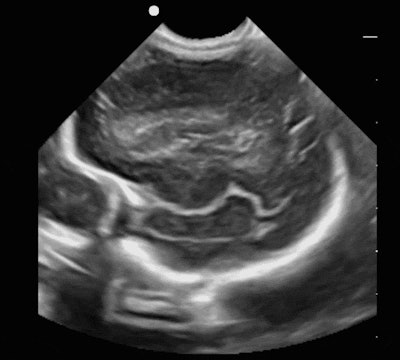

The SonoSim LiveScan Neonatal & Infant Neurosonography training package is designed to improve medical professionals' knowledge and use of ultrasound for diagnosis in pediatric care. SonoSim is also releasing three new training modules for pericardiocentesis, thoracentesis, and paracentesis. The training in ultrasound-guided procedures may help decrease the rate of needle-based complications, the company said.